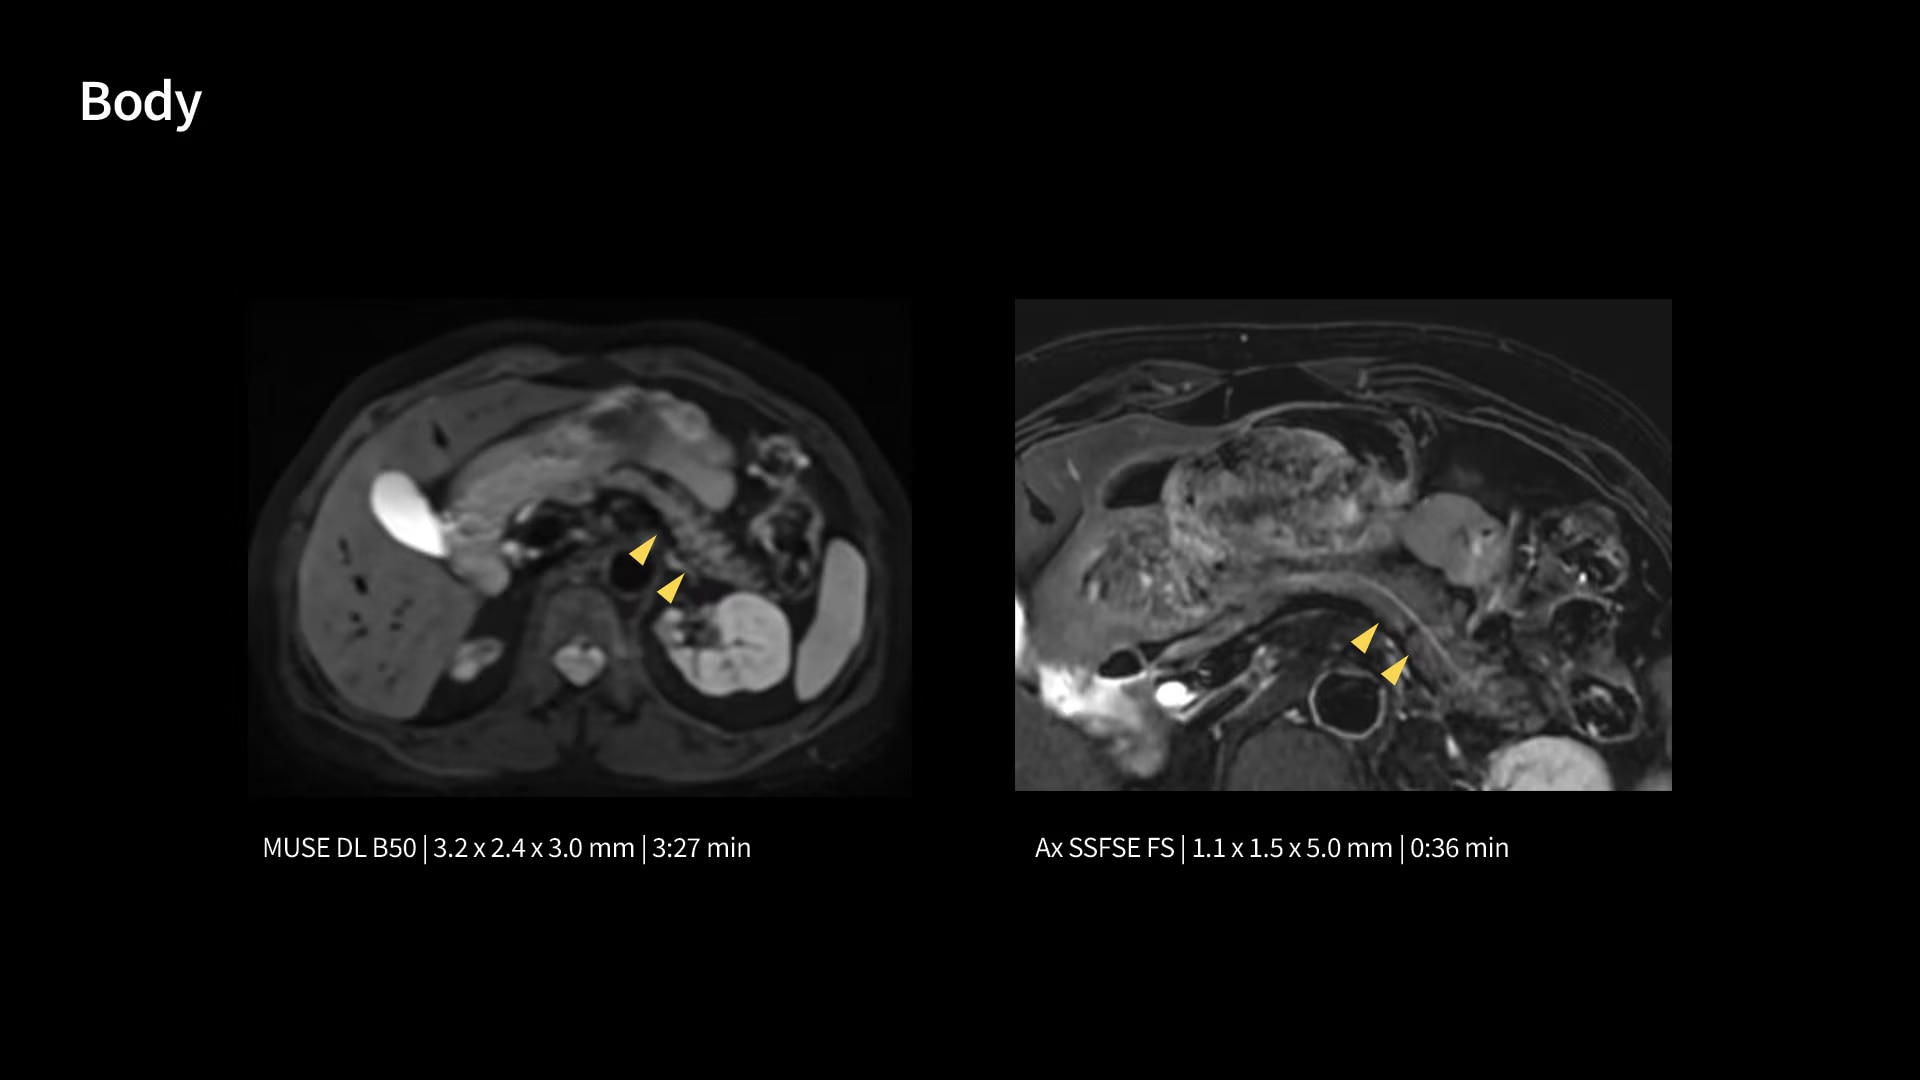

In oncological assessments, diffusion imaging is a critical clinical indicator. SIGNA Sprint offers clearer diffusion, reduced distortion and improved SNR.¹

With GE HealthCare's comprehensive suite of deep-learning solutions integrated into SIGNA Sprint, you can unlock the full potential of your MRI system. No need for complicated patient setups or imaging protocols. The exceptional intelligence of our AI solutions offer multiple benefits, with AIR Recon DL giving pin-sharp images, Sonic DL accelerating scans up to 12x, and AIR x enabling automated slice placement. All helping to enhance your department’s workflow efficiency, increase patient throughput, and get the diagnostic clarity you need, faster.¹ Meaning you can spend more time on what truly matters—personalized patient care, enabling optimized treatment plans and treatment response monitoring—ultimately, supporting better clinical outcomes.